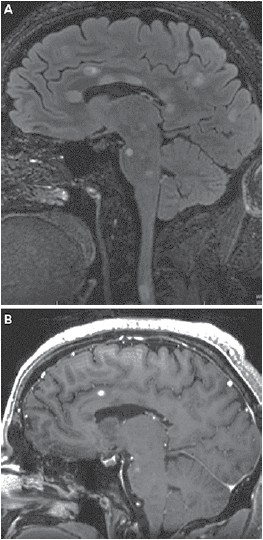

Masculino, 18 anos, sem antecedentes, foi admitido no hospital com quadro de hemiparesia à esquerda e incoordenação de início há uma semana e não progressiva. Ao exame apresenta nistagmo horizontal bilateral, hemiparesia braquio-crural à esquerda com liberação piramidal e dismetria em membros superiores bilateralmente. Realizou ressonância magnética de encéfalo que se encontra a seguir. Líquor apresenta 10 células, 94% de linfócitos, 48 mg/dL de proteínorraquia e presença de bandas oligoclonais. Paciente recebeu pulsoterapia com dose adequada de corticoide com melhora dos sintomas. Assinale a alternativa que apresenta, correta e respectivamente, o diagnóstico deste paciente e, com base neste quadro clínico, a melhor opção terapêutica inicial para ele.